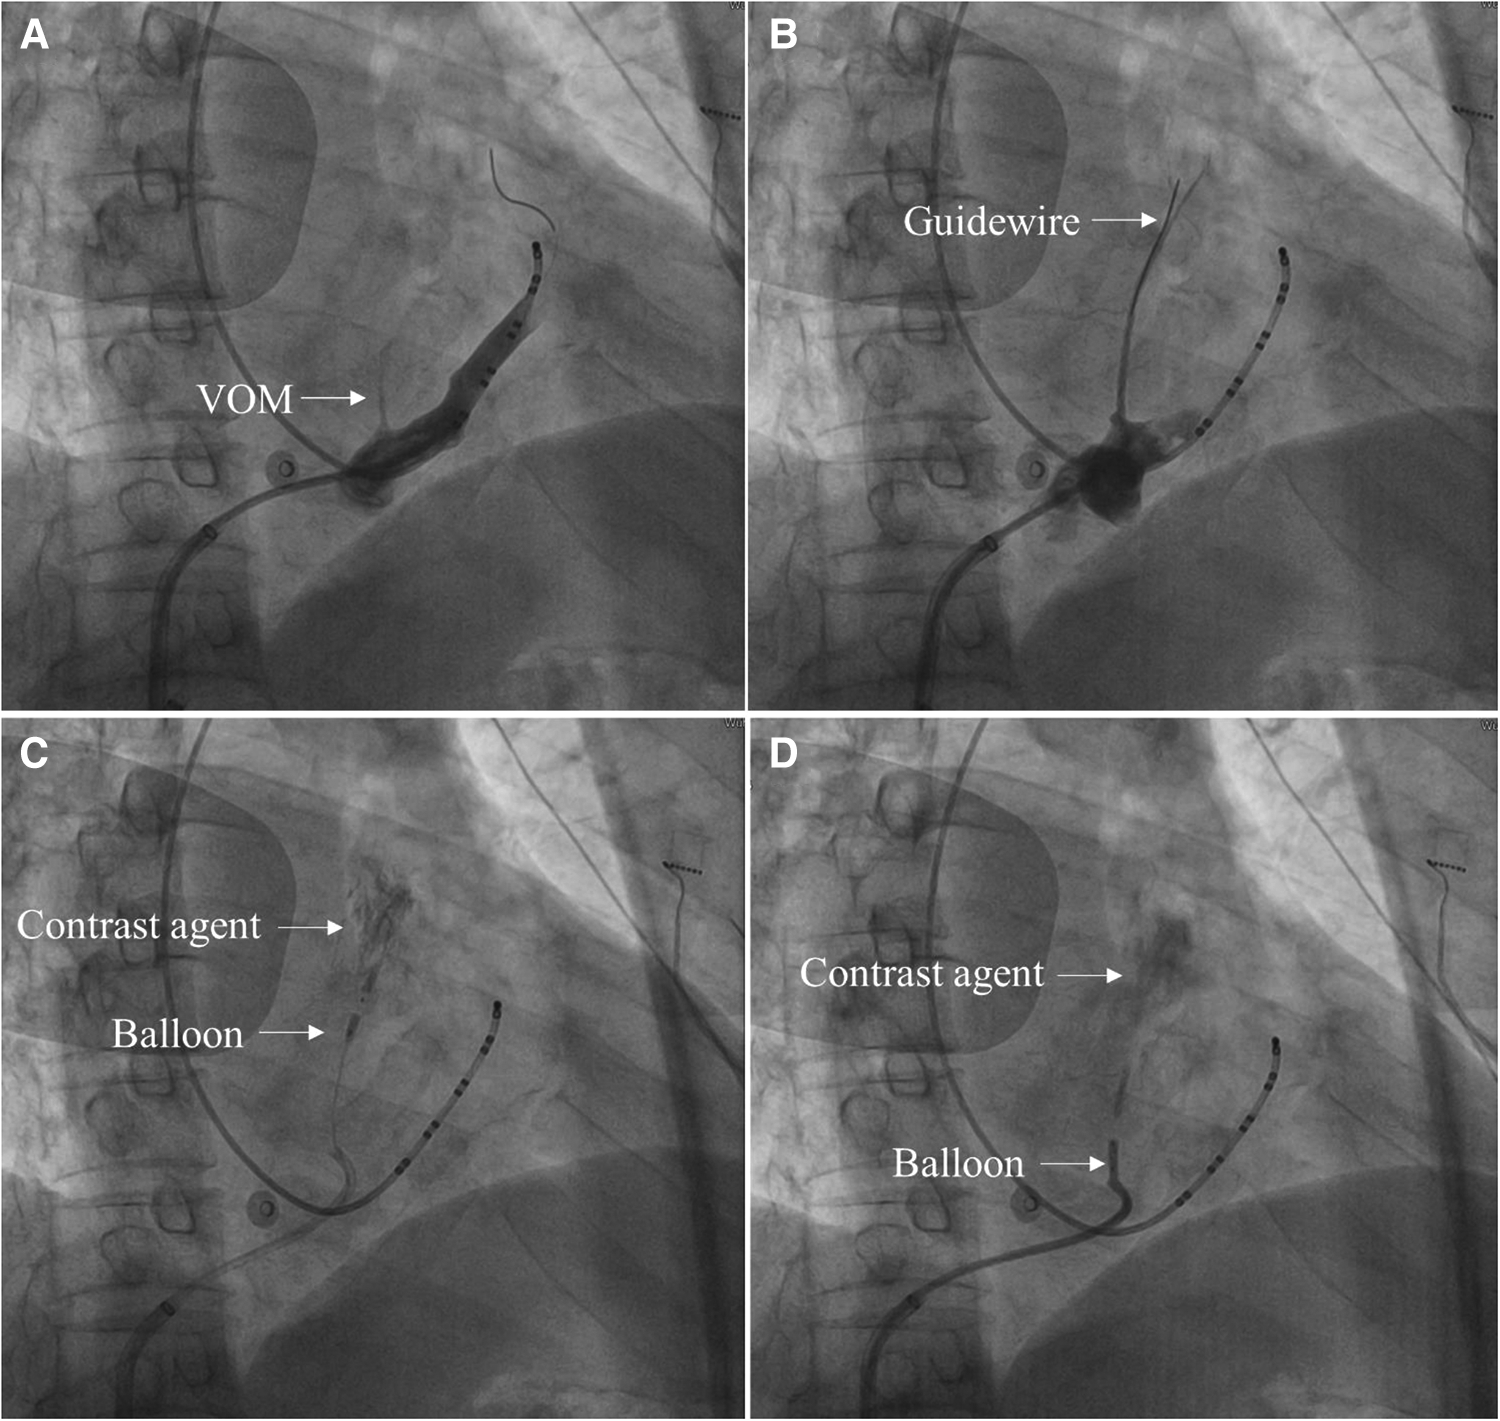

A 6F JR 3.5 guiding catheter was advanced to the CS vein, and CS vein angiography showed VOM (Figure 1A).

- 2.4.2

The guiding catheter was advanced close to the proximal end of the VOM, then gently ran a guidewire to the distal end of the VOM (Figure 1B).

- 2.4.3

Approximately 3–6 ml of anhydrous ethanol was slowly injected into the distal end of the VOM through a dilated balloon catheter (Figure 1C).

- 2.4.4

Another 3–6 ml of anhydrous ethanol was slowly injected after the withdrawal of the balloon catheter to the proximal end of the VOM (Figure 1D).

- 2.4.5

When VOM angiography was performed, the ethanol-infused myocardium was stained with contrast agents (Figures 1C,D).

Figure 1

The primary process of the VOM-EI procedure in 30° right anterior oblique views. (A) CS vein angiography showed VOM (Arrow indicates the VOM). (B) A guidewire was advanced to the distal end of the VOM (Arrow indicates the guidewire). (C) After the balloon was dilated at the distal end of the VOM and injected with anhydrous ethanol, local myocardial staining was observed (Arrow indicates the dilated balloon at the distal end of the VOM and the myocardium stained with a contrast agent, respectively). (D) After the balloon was dilated at the proximal end of the VOM and injected with anhydrous ethanol, local myocardial staining was observed (Arrow indicates the dilated balloon at the proximal end of the VOM and the myocardium stained with a contrast agent, respectively).